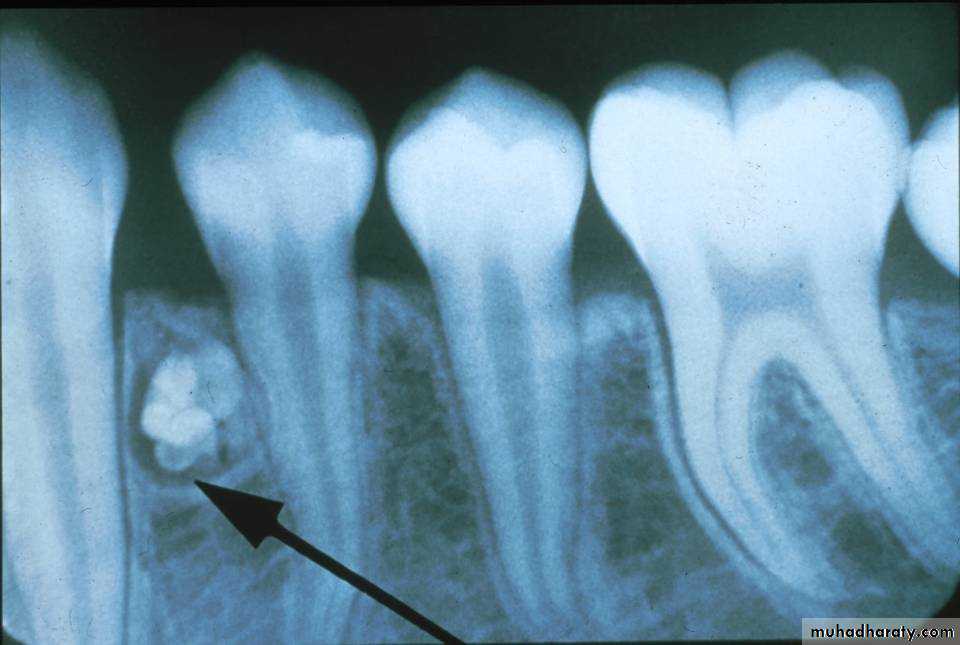

• CEOTs occur as radiolucent lesions with/without opaque foci.

• They are usually well-circumscribed and may be unilocular or multilocular.• Slightly over 50 % of the CEOTs are associated with an unerupted tooth.

Calcifying Epith. Odontogenic TumorRadiographical features

• Early lesions are radiolucent with smooth, well-defined contours.

• Later a well-defined radiopaque appearance develops.• The compound type shows apparent tooth shapes while the complex type appears as a uniform opaque mass with no apparent tooth shapes present.

Odontoma

Radiographical features